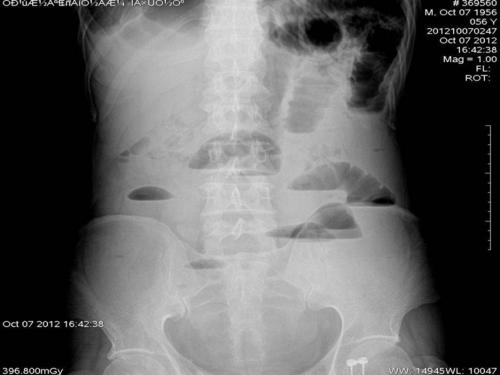

肠梗阻片子,肠梗阻ct

如何辨识肠梗阻

x 线片多可发现肠腔充气扩张或低位肠梗阻,造影显示典型的狭窄段,扩张

小肠梗阻 特点:气液平面.

肠梗阻平片

肠梗阻腹部平片